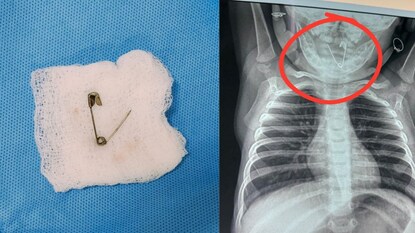

चिपळूण: लहान मुलांच्या बाबतीत पालकांचा एक क्षणाचा हलगर्जीपणा किती जीवावर बेतू शकतो, याचा प्रत्यय दापोली येथील एका घटनेवरून आला आहे. एका सात महिन्यांच्या बाळाला गेल्या महिनाभरापासून सर्दी-खोकल्याचा त्रास होत होता. मात्र, साध्या वाटणाऱ्या या त्रासामागे चक्क घशात अडकलेली 'सेफ्टी पिन' असल्याचे समोर आले. वालावलकर रुग्णालयातील तज्ज्ञ डॉक्टरांच्या पथकाने अत्यंत जोखमीची शस्त्रक्रिया यशस्वीरीत्या पार पाडून या बाळाला नवे आयुष्य दिले आहे.

महिना झाला तरी बाळाला सर्दी - खोकल्याचा त्रास होत होता. औषधोपचार केला तरी बाळाचा त्रास कमी होत नसल्याने पालकांनी दापोलीतील बालरोगतज्ज्ञांकडे धाव घेतली. तिथे डॉक्टरांनी एक्स-रे काढण्याचा सल्ला दिला असता, बाळाच्या घशात एक उघडी सेफ्टी पिन अडकल्याचे निदर्शनास आले. परिस्थितीचे गांभीर्य ओळखून डॉक्टरांनी बाळाला तातडीने वालावलकर रुग्णालयात नेण्यास सांगितले.

रुग्णालयात पोहोचताच कान-नाक-घसा विभागाच्या डॉ. सीजा यांनी प्राथमिक तपासणी केली. क्षणाचाही विलंब न लावता बाळावर शस्त्रक्रिया करण्याचा निर्णय घेतला. तपासणीदरम्यान असे लक्षात आले की, आधी घशात दिसणारी ही पिन आता अन्ननलिकेपर्यंत खाली सरकली होती. सर्वात मोठी भीती ही होती की, सेफ्टी पिन उघडी असल्यामुळे ती अन्ननलिकेला छिद्र पाडू शकत होती, जे बाळाच्या जिवासाठी अत्यंत घातक ठरू शकले असते. मात्र, तज्ज्ञ डॉ. राजीव यांनी 'ईसोफॅगोस्कोपी' (Esophagoscopy) या प्रक्रियेद्वारे अत्यंत कौशल्याने ती पिन बाहेर काढली. सात महिन्यांच्या लहान बाळाला भूल देणे हे सर्वात मोठे आव्हान होते, जे रुग्णालयाच्या भूलतज्ज्ञांनी यशस्वीरीत्या पेलले.

शस्त्रक्रियेनंतर बाळाला रुग्णालयातील अद्ययावत बालरोग अतिदक्षता विभागात ठेवण्यात आले होते, जिथे त्याची रिकव्हरी जलद गतीने झाली. कान-नाक-घसा तज्ज्ञ, भूलतज्ज्ञ आणि बालरोगतज्ज्ञ यांच्या एकत्रित प्रयत्नांमुळे हा चमत्कार घडला आहे. अत्याधुनिक यंत्रसामग्री आणि तज्ज्ञ डॉक्टरांमुळे वालावलकर रुग्णालय कोकणातील रुग्णांसाठी खऱ्या अर्थाने वरदान ठरत आहे. अन्ननलिकेत अडकलेली उघडी सेफ्टी पिन अत्यंत गुंतागुंतीच्या शस्त्रक्रियेद्वारे बाहेर काढून डॉक्टरांनी या बाळाला मृत्यूच्या दाढेतून सुखरूप बाहेर काढले आहे.